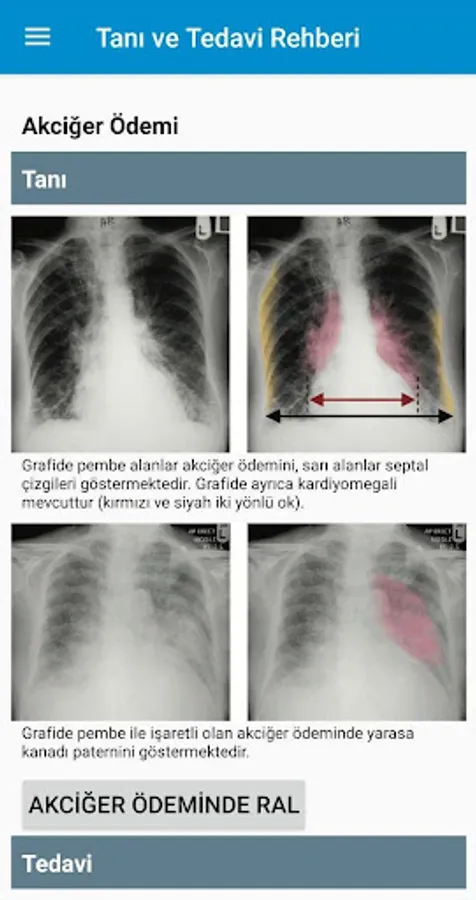

2. In each disease, there are examinations and imaging that will lead physicians to the diagnosis.

5. In some diseases, respiratory sounds or heart sounds are also included along with ECG or radiography images.